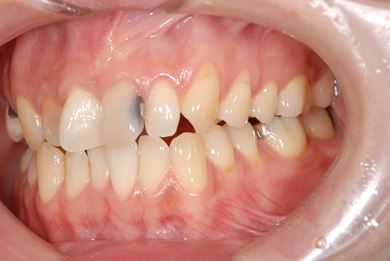

インプラント治療+セラミック治療

| カテゴリー | 【インプラント治療】【セラミック治療】 | ||||||||||||||||||||||||||||||||

| 性別/年齢 | 女性 / 30歳 | ||||||||||||||||||||||||||||||||

| 主訴 | 虫歯を治して欲しい。 | ||||||||||||||||||||||||||||||||

| 治療内容 | インプラント1本、メタルボンドセラミッククラウン1本、オールセラミッククラウン2本(オールセラミック用土台2本) | ||||||||||||||||||||||||||||||||

| 総治療費 | 703,238円 | ||||||||||||||||||||||||||||||||

| 治療期間 | 1年6ヶ月 |